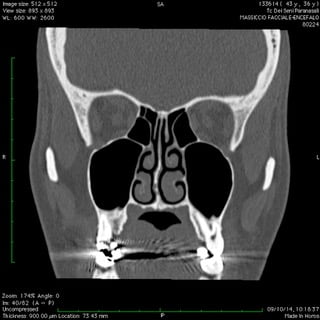

Anche nelle sinusiti la peculiare morfologia anatomica delle strutture coinvolte, cavità ossee, consente nella maggior parte dei casi latenze di esordio molto ritardate rispetto il primitivo insorgere patologico palesandosi così in avanzate fasi di compromissione .

Nelle forme croniche, cioè di malattia stabile nel tempo, i seni paranasali diventano “ siti di decantazione”, ovvero di ristagno e moltiplicazione,per germi di vario genere dando vita così ad un persistente primario serbatoio contaminante sia le vie aeree che quelle digestive.